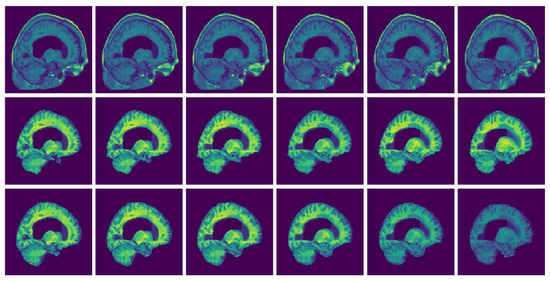

2.2.1. Preprocessing

3. Results

Consistency Analysis of the GUBS across Different Data Sets